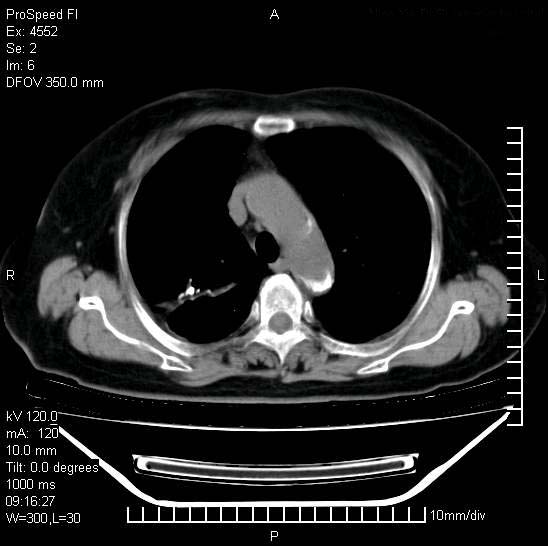

标题: CT15528:女性,79岁,近几日晚上高热,39度,仍咳少量血

十几年前曾患肺结核,一周前突咳血约100ml,中性粒细胞稍高,诊断两上肺陈旧结核,下肺炎症,给予抗炎治疗,近几日晚上高热,39度,仍咳少量血,4天前ct及今天ct上传。

今天ct

短短几天内,病变范围明显增多扩大,以左侧明显,而且双侧出现胸水,还是考虑感染.

短短几天内,病变范围明显增多扩大,以左侧明显,而且双侧出现胸水,我更多考虑左侧中心性肺癌并并阻塞性不张及肺炎,炎症变化也太快了!

1)两肺结核并感染。2)不排除左肺上叶中央型肺癌并阻塞性肺炎、肺不张可能;建议行纤支镜检查。3)右肺门及纵隔淋巴结肿大。4)双侧胸腔积液。